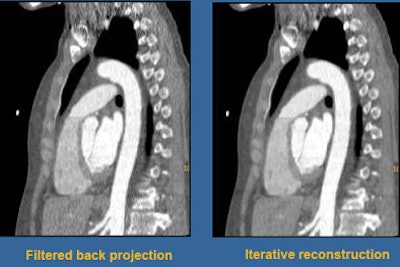

![]() |

| Axial scan of patient with thoracic aortic aneurysm seen on capital (left) and axial (right) views. Some photon starvation can be seen in the shoulder region, a common limitation of the axial scanning technique. |